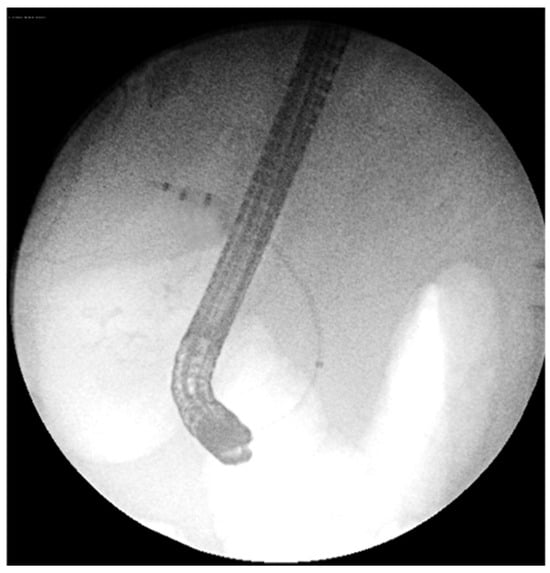

13.02: Abdominal ultrasound identified only gallbladder microlithiasis, without bile duct dilation (Figure 1).

Figure 1. Abdominal ultrasound (13.02.2025): gallbladder microlithiasis, no bile duct dilation.